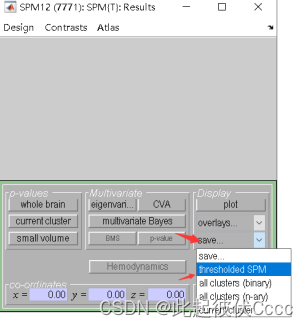

4.点击Done,之后按下图进行选择

5.出现结果

6.将结果保存,点击Save->threshold SPM,之后再给文件取名字回车即可